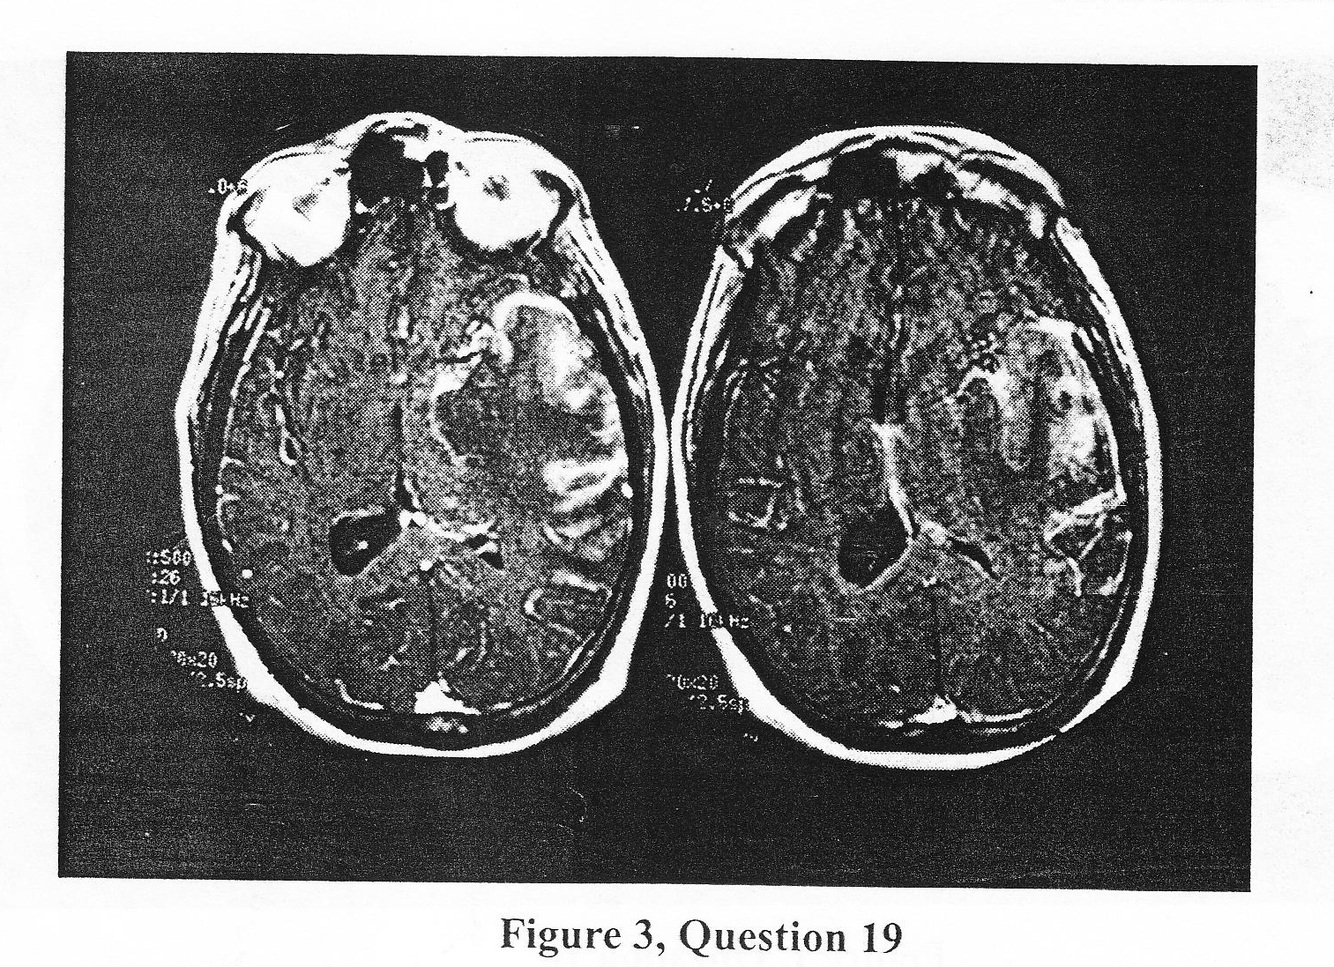

A 35-year-old wihte male complins of fever and headache. He begins to notice odd smell and his wife feels hisbehaviour is odd. Two days later he has a generalized seizure and is brought to the emergency room. On examination, you note a confused state with normal level of consciousness, right-sided weaness, and right Babinski sign. Intra cranial imaging is obtained (Figure 3). Cerebrospinal fluid (CSF) reveals 30 polymorphonuclear cells, protein of 120, glucose of 50. You NEXT : a. Begin intravenous acyclovir or equivalent agent, obtain an EEG, ask for a PCR on suspected agent DNA in CSF

b. Begin broad spectrum antibiotics and await CSF cultures

c. Perform emergent temporal lobe tumor

d. Order a chest x-ray and a purified protein derivative skin test for tuberculosis, and assure CSF sample is properly cultured for mycobacterium tuberculosis

a. Begin intravenous acyclovir or equivalent agent, obtain an EEG, ask for a PCR on suspected agent DNA in CSF